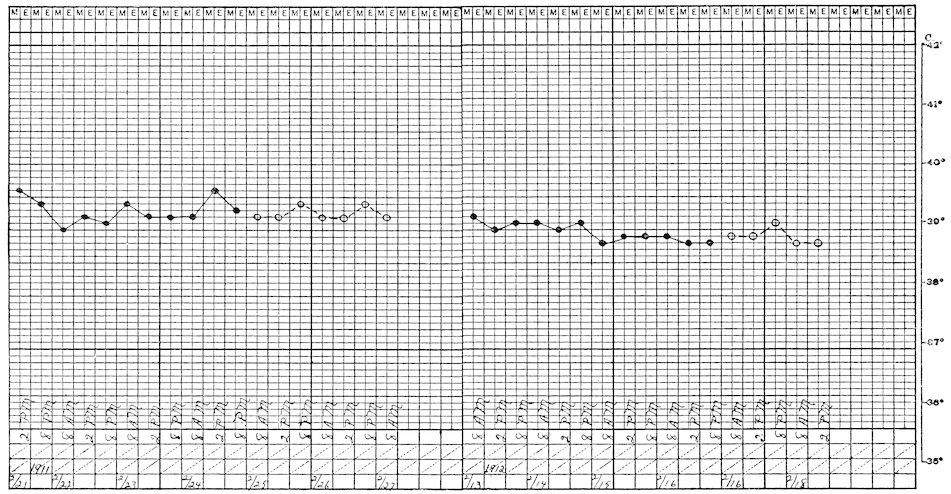

Columbæ:

Columbidæ:

Ocyphaps lophotes,